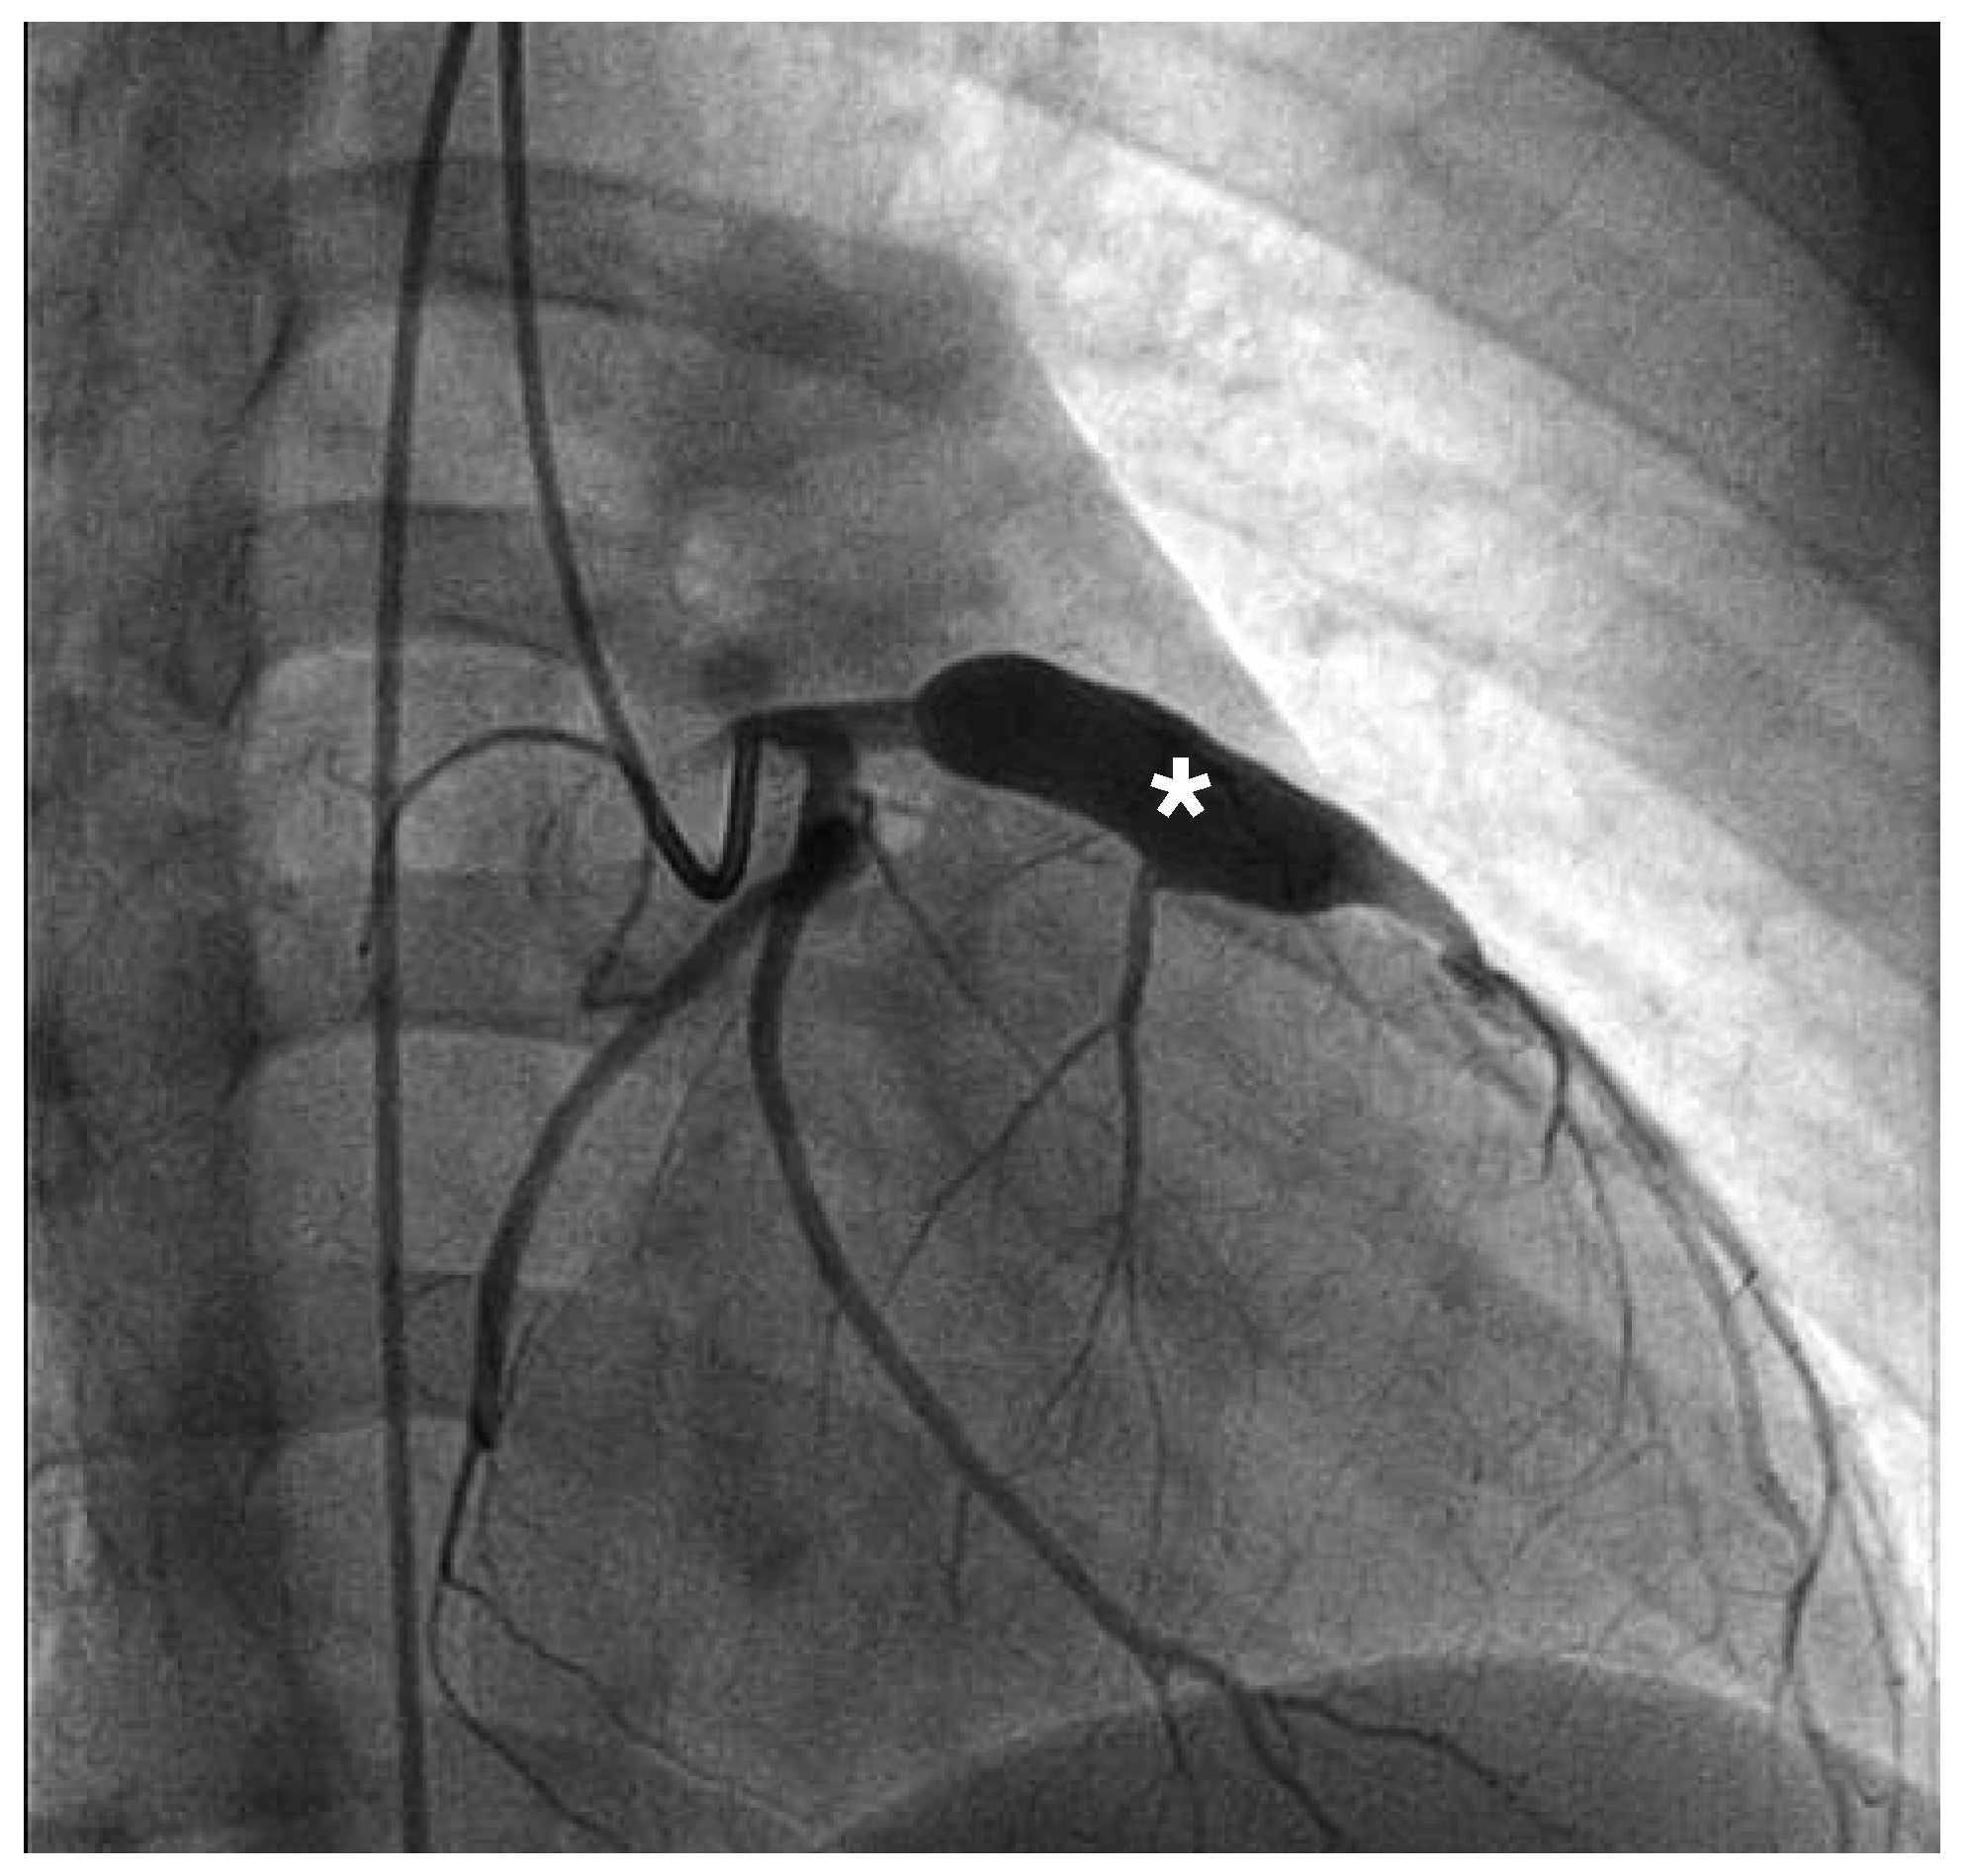

On the tenth day, we performed transthoracic echocardiography (Figure 1 and Figure 2), which revealed normal biventricular size and function, without hypokinesia. There was no pericardial effusion, no valvular disease, but a proximal enlargement of the left anterior descending coronary artery (LAD) was visualised. On the same day, because all these elements suggested Kawasaki disease (KD), treatment with intravenous polyvalent immunoglobulin (IVIG 2 g/kg as a single infusion: Privigen 70 g) and high-dose aspirin (80 to 100 mg/kg/d: 750 mg four times a day for eight days) was started, with rapid resolution of symptoms and apyrexia within 24 hours. Cardiac computed tomography (CT; Figure 3) showed three-vessel aneurysmal coronary artery disease (CAD) including a giant aneurysm of the proximal LAD (9 mm), an aneurysm of the circumflex artery (6 mm) and two aneurysms of the right coronary artery (4 and 5 mm). There was no vascular involvement in the cerebral and abdominal magnetic resonance imaging (MRI).

Figure 4.

Coronary angiography with partial remodelling six months later. Only the left anterior descending artery aneurysm (*) persists.